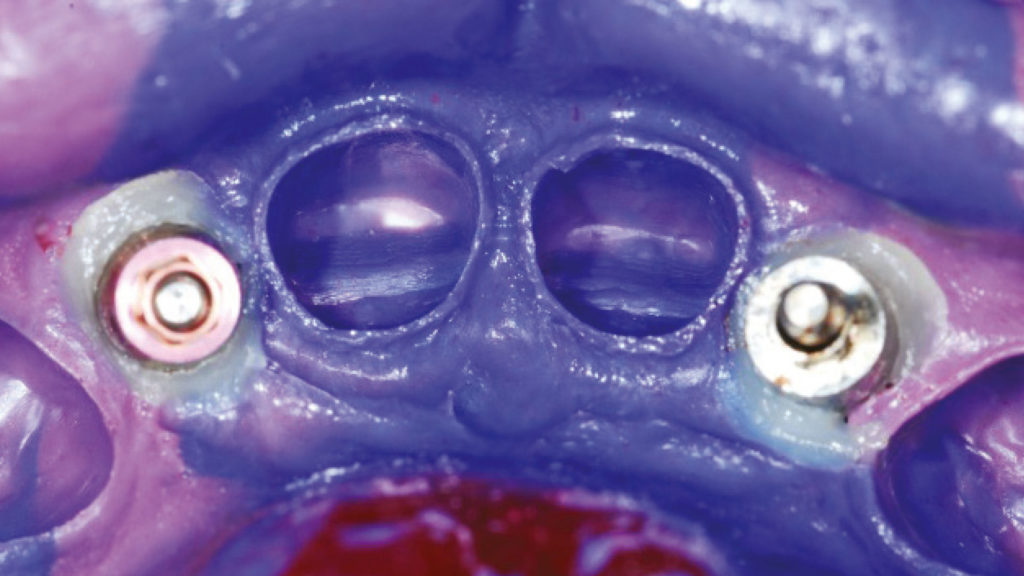

Die Patientin war mit vier älteren Metallkeramikkronen im Oberkieferfrontzahngebiet versorgt (Abb. 14). Nach dem Entfernen der alten Versorgungen und der beiden nicht mehr erhaltungswürdigen lateralen Pfeilerzähne sowie dem Inserieren zweier Implantate in regio 12 und 22 (Abb. 15 und 16) soll dieser Fall mit vier Vollkeramikkronen gelöst werden: zwei Kronen auf natürlichen Zähnen (11 und 21) und zwei durchverschraubte Kronen auf Implantaten in regio 12 und 22. Da der ästhetische Anspruch nicht so hoch ausfallen konnte, wir aber aufgrund der Implantatkronen eine höhere Festigkeit benötigen, fiel die Wahl auf das HTML Zirkonoxid (wir erinnern uns: Hochtransluzentes (HT) Multilayer (ML) Zirkonoxid mit einer Festigkeit von 1200 MPa) in der Farbe A2. Die daraus gefertigten Gerüste werden palatinal vollanatomisch belassen und lediglich vestibulär reduziert (anatomisches Cut-back). Dabei wird bereits auf die Anlage bestimmter opaleszierender Dentinstrukturen geachtet, um die naturnahe Reproduktion der Kronen zu vereinfachen (Abb. 17a und b). Um die dreidimensionale Tiefenwirkung zu verbessern, wurden mittels ILS-Technik auf den reduzierten Vestibulärflächen des Zirkonoxidgerüsts Internal Stain Incisal Blue1 um die Mamelons herum, und Internal Stain Fluoro sowie Internal Stain Salmon Pink am Zervikalrand aufgetragen (Abb. 18a bis c). Für ein ausgeglicheneres Chroma kommt in Richtung zervikal und in der Mitte des Zahnkörpers noch Internal Stain A+ zum Einsatz. Schließlich wird die vestibuläre Morphologie mit einem überschaubaren Microlayering vervollständigt, für das Luster-Massen aber auch eine Zervikal-Masse zur Anwendung kommen (Abb. 19a und b):

- für den Opaleszenz-Effekt Luster Aqua Blue1

- für den Körper und die Inzisalbereiche Luster LT0

- für die Zervikalbereiche Cervical CV-2

- für die approximalen Flanken Luster ELT3